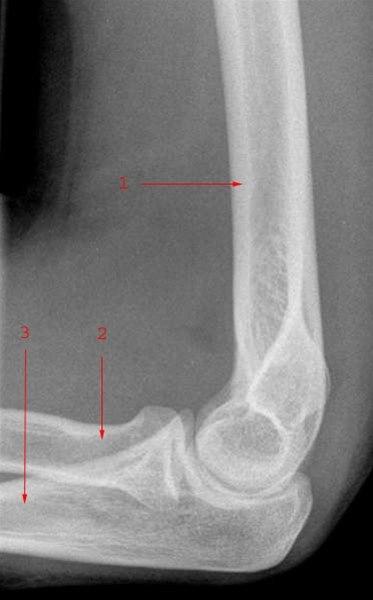

Beinbrudd i albuen

- Mange ulike beinbrudd kan oppstå i albuen

- Albuen ute av ledd

- Brudd i nedre del av overarmsbenet

- Brudd i capitellum humeri

- Brudd i olecranon

- Brudd i collum radii

- Brudd i caput radii

- Brudd i underarmen

- Foreligger mistanke om brudd, vil du umiddelbart bli henvist til sykehus for å få tatt røntgenbilde